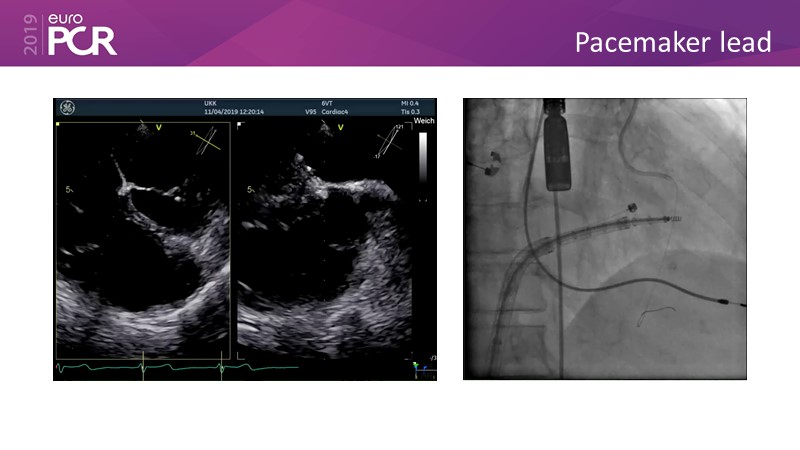

Addressing tricuspid regurgitation with annular reduction: the Cardioband tricuspid system

Consult this session to understand how patients with tricuspid regurgitation and annular dilatation can benefit from Cardioband system...

- To understand how patients with tricuspid regurgitation and annular dilatation can benefit from Cardioband system

- To learn how to perform a good echo workup for Cardioband tricuspid system